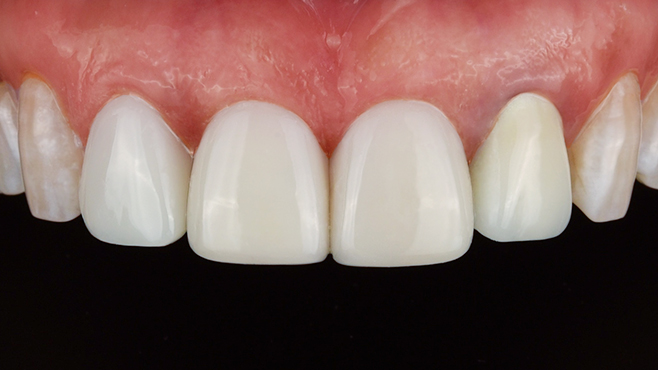

환자를 향한 진심,

완성도 높은 결과

환자의 상태를 세심하게 살피고,

글로벌 스탠다드에

맞춘

진단과

치료 과정을 통해 보다 안전하고

완성도

높은 결과를 만듭니다.